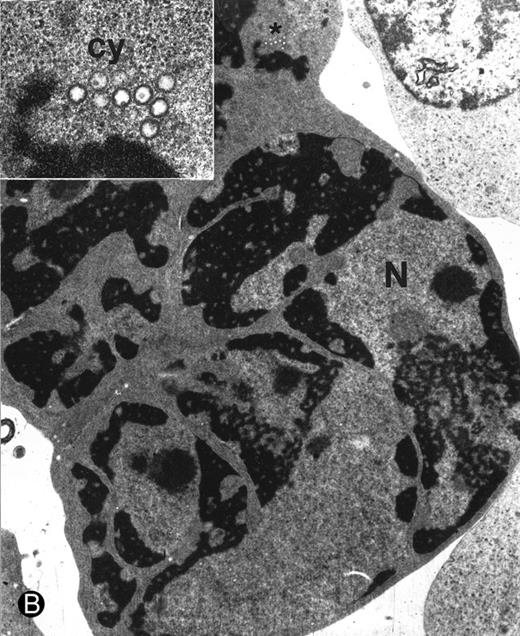

Morphologic examination of syncytia in HHV-7–infected SupT1 cultures (8 day pi) by light (A) and electron (B through E) microscopy. (A) Field with three syncytia and various single cells. (B) Multinucleated syncytium with an intact morphology. (C) Particular of a necrotic syncytium with vacuolized cytoplasm and initial discontinuation of the plasma membrane. Also note the lack of nuclear chromatin condensation. In (B) and (C), virions appear as dark points (asterisks). (D) Ringed nucleocapsids with an electron-dense core in the cytoplasm of a necrotic syncytium. (E) Particular of a syncytium in advanced stage of necrosis (bottom left), releasing mature virions (asterisks) in proximity of an intact cell (top right). N, nucleus; cy, cytoplasm; v, vacuole; pm, plasma membrane. Original magnifications: (A) ×400; (B and C) ×6,000; (D) ×36,000; and (E) ×7,000.

At ultrastructural examination, a significant fraction of syncytia still maintained an intact appearance with little loss of cytoplasmic and nuclear organization despite the presence of numerous virions in the cytoplasmic compartment (Fig 2B). Although cytoplasmic virions were also observed in single cells, all syncytia invariably contained large amounts of typical herpesvirus nucleocapsids, which appear as single, ringed particles with an electron-dense center representing the core.27 28

However, most syncytia exhibited a vacuolized cytoplasm and discontinuation of the plasma membrane with lack of chromatin condensation, which are considered typical ultrastructural features of necrosis (Fig 2C). The morphologic features of necrosis were always associated with the presence of nucleocapsids in the cytoplasm (Fig 2D) and often with the release of mature virions in the extracellular space (Fig 2E). To ascertain that the ultrastructural features of syncytia shown above were truly representative of HHV-7 infection, various syncytia obtained from two separate experiments were analyzed. The presence of large amounts of cytoplasmic virions was confirmed in all syncytia examined, strongly suggesting that these giant multinucleated cells represented the major source of viral particles in the culture. Moreover, the majority of syncytia showed morphologic evidences of necrosis, whereas less than 5% showed apoptotic features (Table 1).